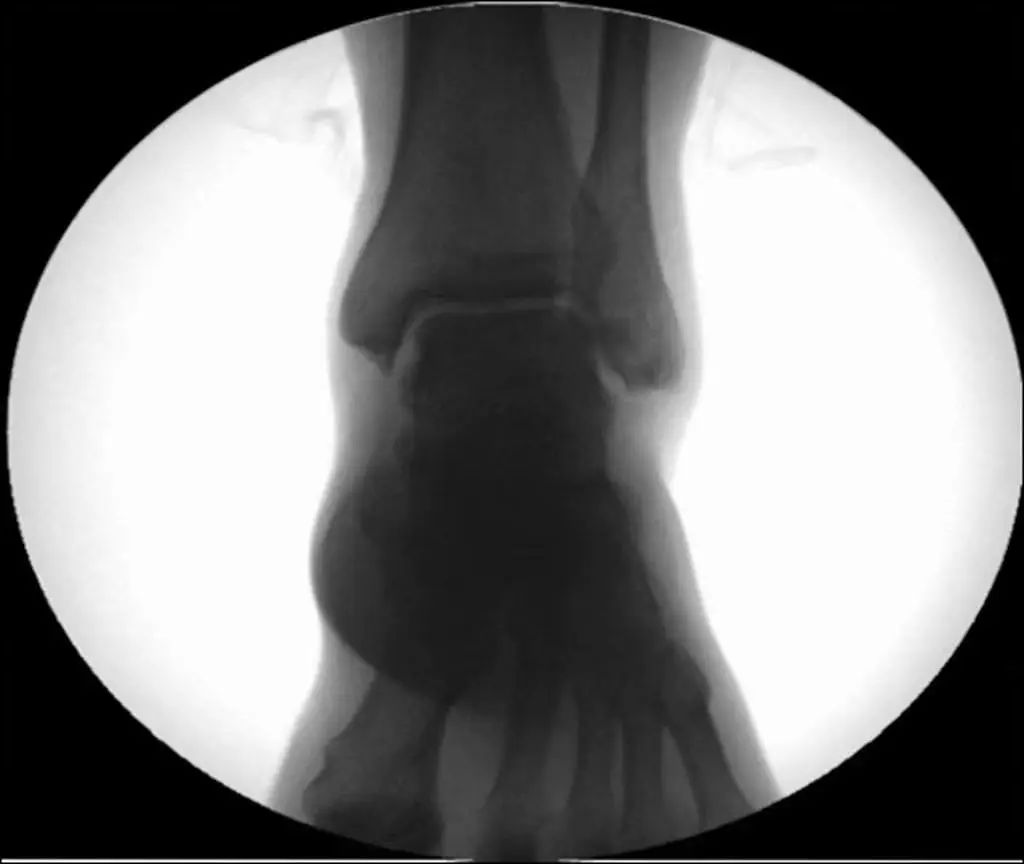

Рентгенодиагностика. Стандартная визуализирующая оценка голеностопного сустава должна включать 3 фазы: переднезаднюю (рис. 8), точку голеностопного сустава (внутренняя ротация 15°) (рис. 9) и боковую (рис. 10).

При серьезном повреждении голеностопного сустава внутренняя и внешняя лодыжки и таранная кость смещаются на 11 различных градусов (рис. 11).Статические рентгенограммы не точно отражают стабильность голеностопного сустава.Стресс-рентгенограммы и МРТ могут улучшить оценку стабильности голеностопного сустава и повреждения связок (рис. 12).

Рисунок 8 Переднее и заднее положение

Рисунок 9. Точки голеностопного сустава (15° внутренней ротации)

Рисунок 10 Боковое положение

Рис. 11. Смещение перелома, по-видимому, в сочетании с вывихом.

Рисунок 12. Рентгенограмма под нагрузкой (разрыв треугольной связки)